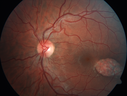

Macular Macroaneurysm with Coats Disease412 views61 year old man with increased leakage from macular macroaneurysm right eyeApr 06, 2019

Macular Macroaneurysm with Coats Disease381 views61 year old man with increased leakage from macular macroaneurysm right eyeApr 06, 2019

Macular Macroaneurysm with Coats Disease369 views61 year old man with increased leakage from macular macroaneurysm right eyeApr 06, 2019

Macular Macroaneurysm with Coats Disease376 views61 year old man with increased leakage from macular macroaneurysm right eyeApr 06, 2019